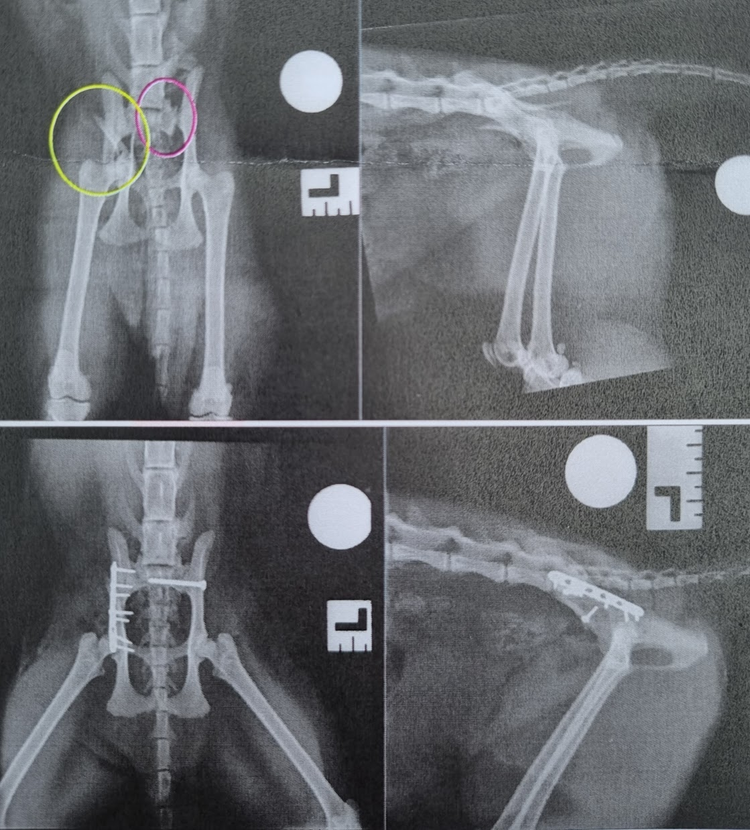

Grumpy was stabilised and underwent advanced imaging of his chest and pelvis (CT imaging and radiography) to determine the severity of his injuries. Imaging revealed multiple fractures to Grumpy’s pelvis. He had fractured his right ilium into several pieces, and had traumatic dislocation/fracture of the left side of his pelvis, leaving his left hemipelvis unattached to the spine.

Both injuries were affecting the weightbearing axis of the pelvis, which meant Grumpy was rendered unable to walk. The left-sided fracture was also very close to vital nerves which provide movement and sensation to the limb. Thankfully, imaging of the chest did not reveal significant injuries that could complicate Grumpy’s anaesthetic.

Surgical stabilisation of the pelvic injuries were necessary to give Grumpy the best chance of a full recovery. To treat Grumpy, the hospital’s team performed surgery to reduce and stabilise the main fractures of his pelvis, and restore early comfort and function. Surgery took over three hours, involved two Orthopaedic consultants, a Veterinary Anaesthetist, and several specialist referral nurses for continuous anaesthetic monitoring and surgical assistance. A screw was used to reduce and re-attach the left hemi-pelvis, and on the right-side the ilial body fracture (which was broken into several pieces) was approached and anatomically reconstructed using bone plates and screws.